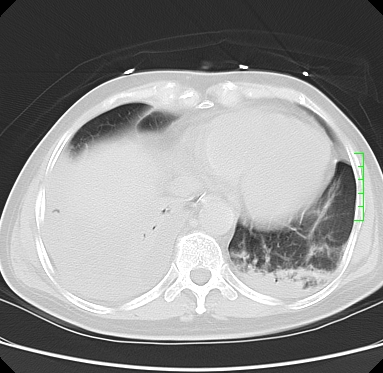

icu病人,几天都没明确诊断。m,76y,咳嗽、咳痰1周,伴气促,右胸痛入院,pe:t38.3c p135 r25 bp135/85。双肺可闻及大量湿罗音,心、腹未见明显异常。诊断:1心衰?2肺部感染?3冠心病?

11号ct

双肺感染性病变,下叶膨胀不全,胸水,左室大。

1)两肺感染性病变(右肺下叶肺脓肿可能)。2)双侧胸腔积液,以右侧为甚。

ards,肺感染性病变,右下叶实变,双侧胸腔积液,右侧为著,叶间胸膜积液,右上肺陈旧性tb纤维灶,左室大。

考虑双肺感染、右肺下叶肺脓肿伴双侧胸腔积液,肺水肿。

考虑:双肺感染、右肺下叶肺脓肿,双侧胸腔积液,肺水肿.请结合临床.